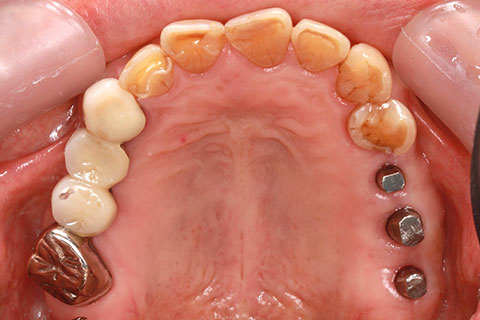

• 症例2

治療前

インプラント埋入時

治療後

年齢・性別

57歳男性

治療期間

3ヶ月

抜歯

なし

治療費

154万円

備考

左上5.6.7 及び左下6.7欠損

治療内容

左上5.6.7と左下6.7欠損部にインプラント埋入

施術の副作用(リスク)

オペによる知覚障害。インプラントによる歯肉炎。インプラント脱落。